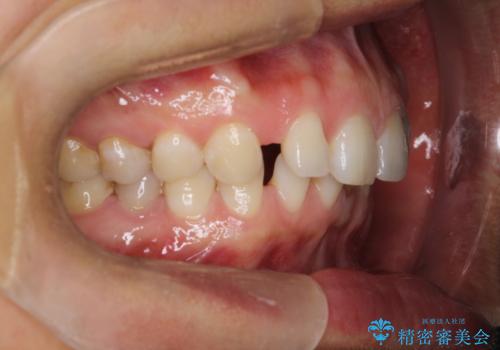

【空隙歯列】ワイヤー矯正で短期間に治療を終えたい

- 歯と歯の間に隙間があることを主訴に来院されました。

短期間での治療終了を希望され、ワイヤー矯正にて治療を行い1年ほどで治療を終了しております。

下顎前歯は矯正後補綴治療を行なっております。